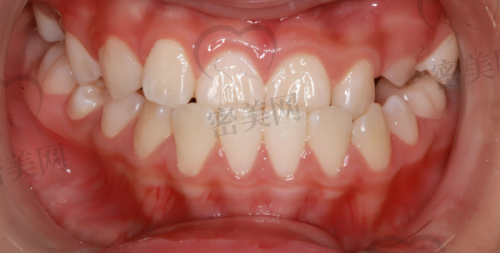

牙博士太仓院区设置了多个科室,包括牙齿洁治、补牙、拔牙、根管治疗、牙齿矫正、儿童牙科、种植牙、牙周病治疗、口腔修复、全口义齿等,几乎涵盖了口腔诊疗的所有常见项目,真正实现“拎包来、带笑走”。特别是种植牙和隐形矫正,是这里的热门项目,接受度非常高。针对怕疼的患者,这里还引入了舒适化口腔诊疗设备,比如微痛麻醉、数字化根管治疗仪、口腔摄影系统等,让看牙这些“怕痛党”少了特别多恐惧感。